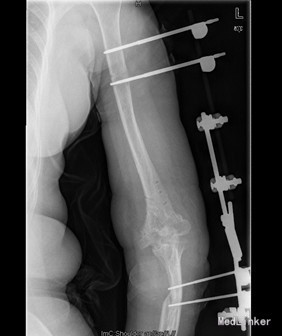

患者女,54岁,因“左肱骨远端陈旧性骨折内固定术后伴左肘关节活动受限1+年”入院。入院前1+年多,患者因车祸致左肱骨远端骨折,后在当地人民医院予以左肱骨远端切开复位内固定术(具体不详)。术后左肘关节活动功能受限,活动度数约为15°-65°左右,遂于今日入我院要求行进一步诊治。

查体:左肘部可见一手术切口瘢痕,皮肤无明显红肿,破溃及静脉曲张等。左肘部及左上臂压痛不明显,未扪及明确异常。左肘部见一约15cm长竖形手术切口瘢痕。左肘关节活动功能受限,活动度数约为15°-65°左右,左上肢肌力及肢体远端运动感觉正常。 辅查:X片示左肱骨远端陈旧性骨折钢板螺钉及克氏针内固定术后。

初步诊断:左肱骨远端陈旧性骨折内固定术后,左肘关节非功能位僵直。 诊疗计划:拟行左肱骨内固定取出,左肘关节松解侧副韧带修复并外支架固定术

术中见左肱骨远端陈旧性骨折,折端已骨性愈合,内固定器钢板、螺钉及克氏针稳定无松动;左侧尺神经,左肘前、后侧关节囊与周围软组织紧密粘连,左肘前外侧见一异位骨化组织,约0.8cm X 1.5cm大小。